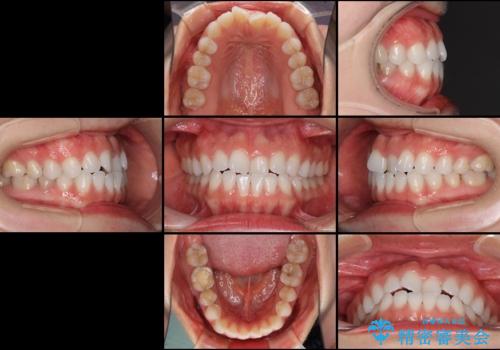

- 上下の前歯の反対咬合を気にして来院された患者様です。

インビザラインを用い、下顎はIPR(歯と歯の間を削る)と歯列全体を後方に移動させ、上顎は前歯を持ち上げることで、反対咬合を改善していくこととしました。

インビザラインによる反対咬合の改善は、上の歯が下の歯を乗り越えていく期間に咬み合わせが非常に不安定となり、治療が長期化することがあります。

こちらの患者様も、一時的に前歯でしか咬めない時期がありましたが、比較的早く咬み合わせが安定し、1年ほどで治療を終えることができました。